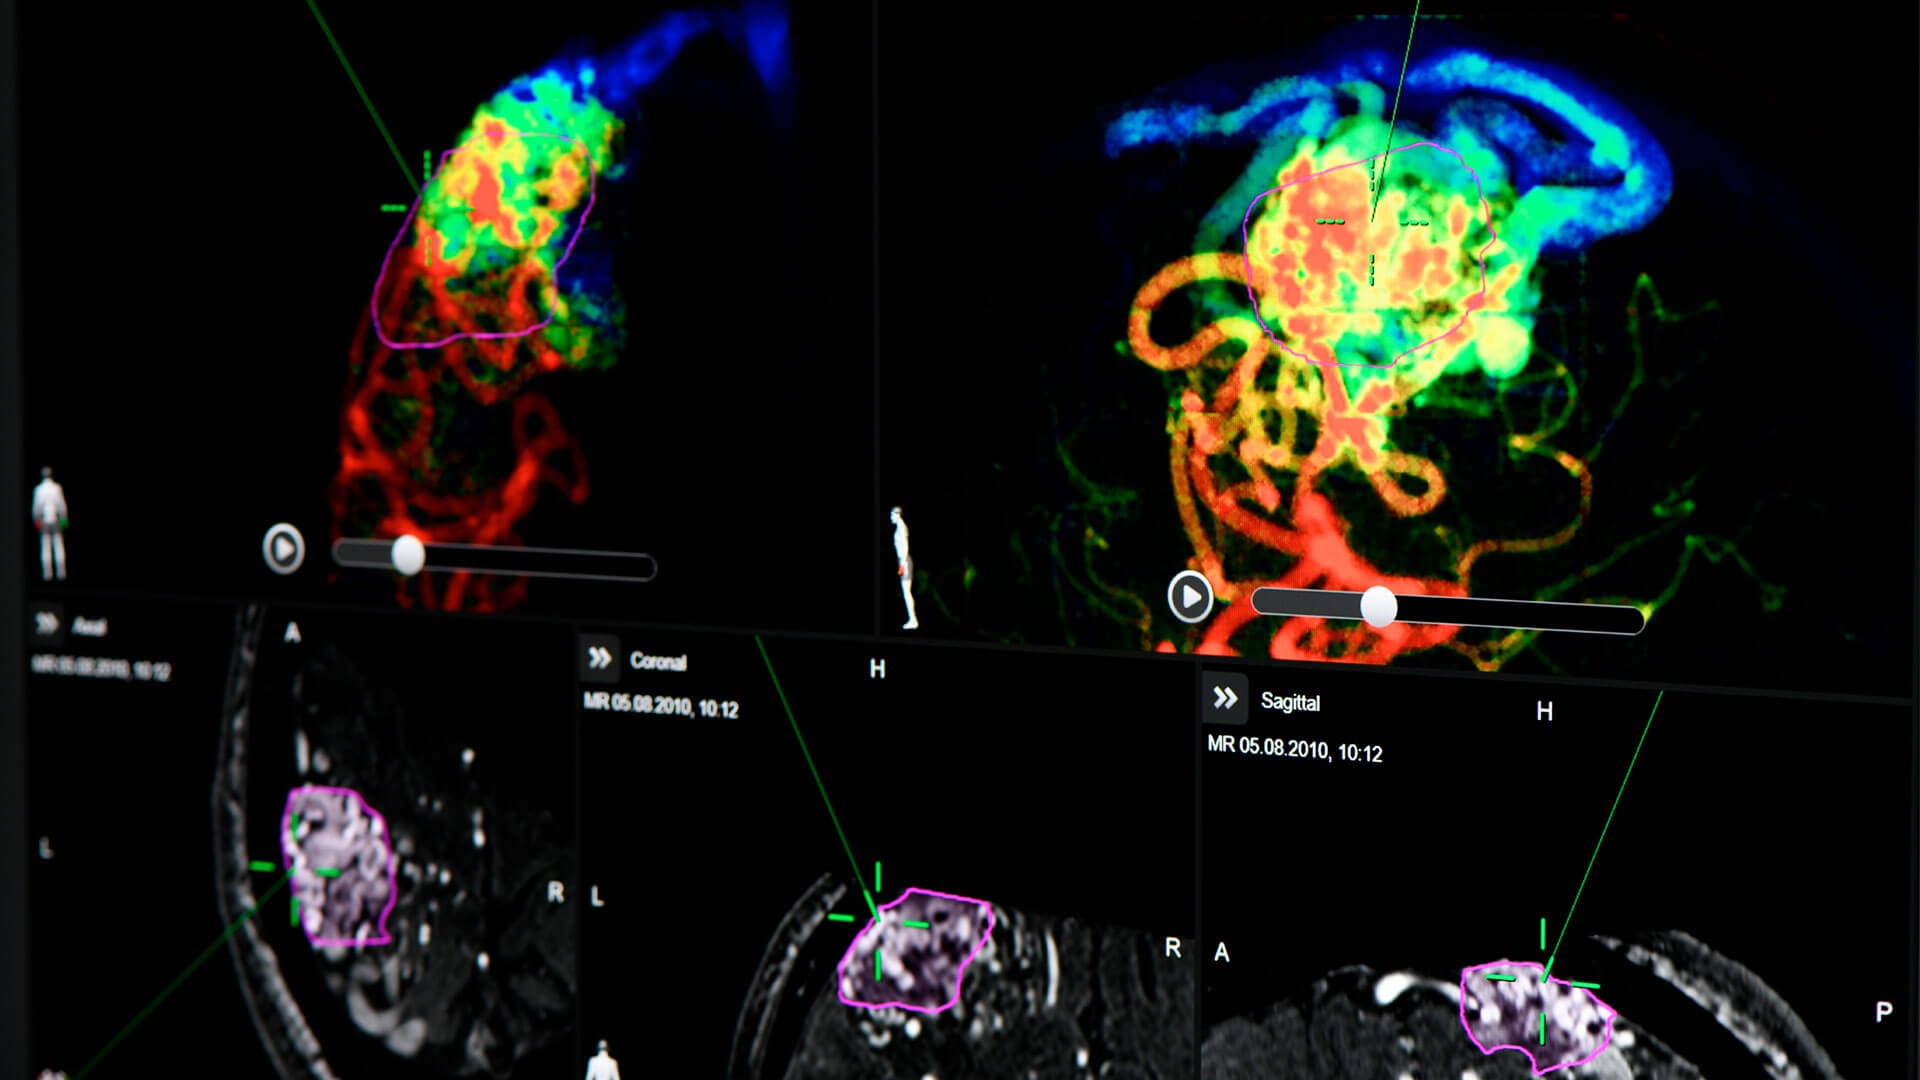

Brainlab neuronavigation combines ease of use with extended functionality tailored to surgeons’ needs